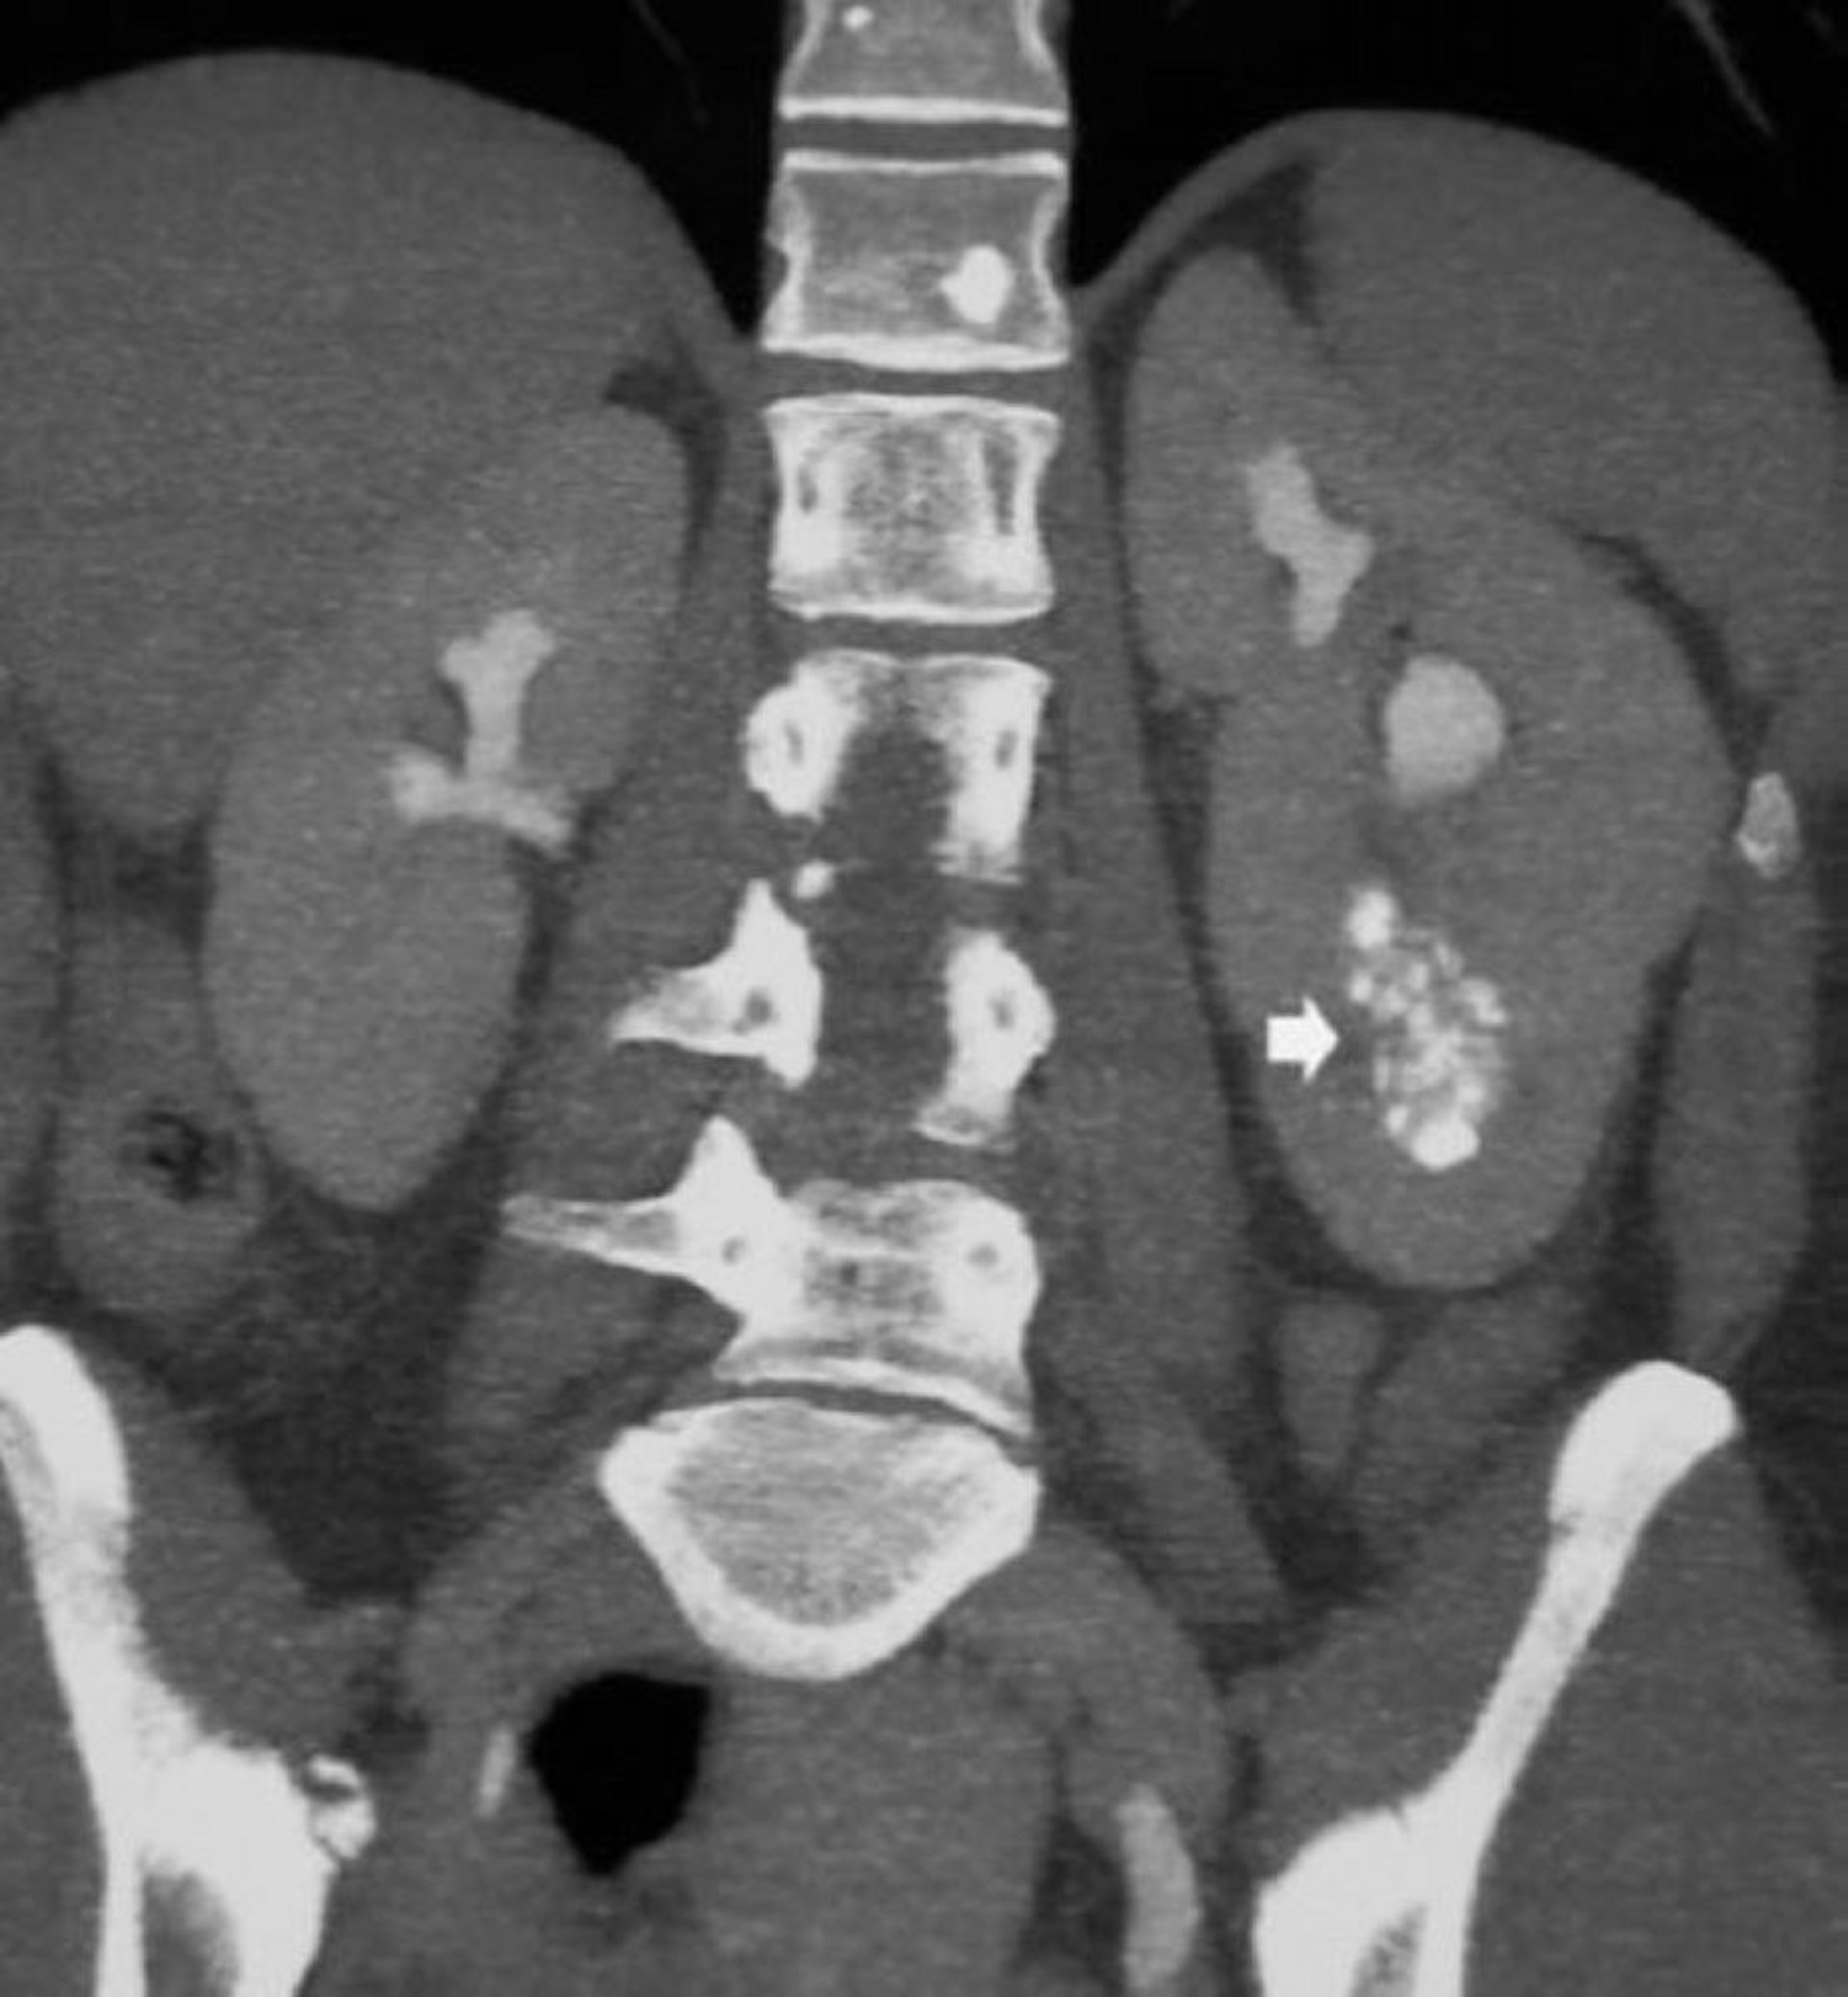

TC coronal sin contraste que muestra nefrocalcinosis medular

Esta imagen muestra la nefrocalcinosis medular y los conductos colectores dilatados llenos de material decontraste en un paciente con nefropatia quística medular (riñón esponjoso mdular) (flecha).